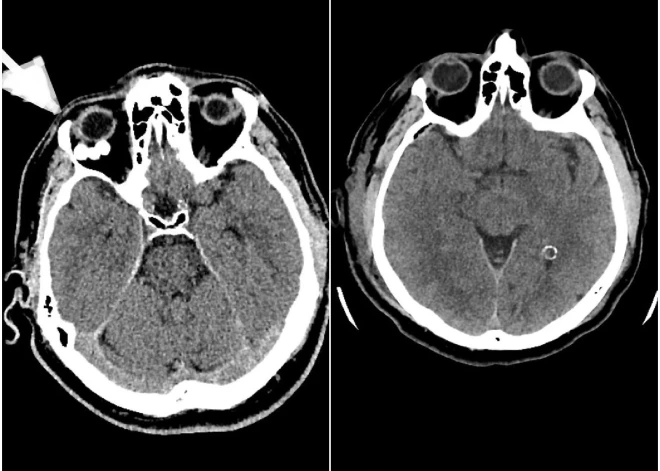

Operācijas laikā neiroķirurģijas komanda veica augstas precizitātes ķirurģisku iejaukšanos – caur galvaskausu tika izveidota aptuveni vienu centimetru liela atvere acs dobuma sienā, kas ļāva piekļūt patoloģiskajam veidojumam un veikt tā pilnīgu rezekciju, nebojājot acs struktūras.

Pēc operācijas pacientam pilnībā izzuda pirmsoperācijas sūdzības, un tika pilnībā saglabātas visas acs funkcijas, tostarp redze un acs kustīgums.